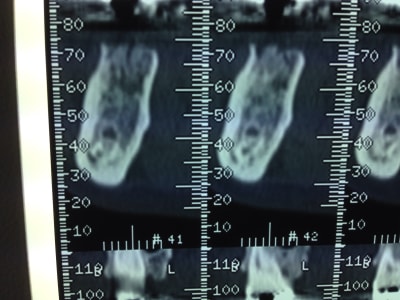

perso, l'imagerie 3D pour moi un cone beam fait partie intégrante de ma planification. Je ne peux pas poser un implant sans prendre un cliché. si il est sectorisé avec un petit l'irradiation est relativement faible. Je ne sais si il existe des recommandations mais si tu as un soucis je pense que l'on te demandera ta planification et tes clichés 3D.

Deux petits gestes simples et systematiques après une extraction :

1)sonder l'alvéole et mesurer les rebords osseux ( sonde implantaire)

2)mesurer les racines ( et photos dans le dossier)

Concernant le CBCT, il faut faire attention ils sont souvent "optimistes" ( déformation de l'image du au faisceau conique), contrairement au scanner ( aucune déformation avec un faisceau parallèle).